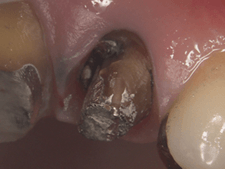

|

|

|

| 虫歯が大きくこのままではうまく被せられません。 | 矯正により歯を引っ張りあげます。 | |

|

|

|

| 歯の周りに丈夫で健康的な歯茎が認められます。 | 綺麗に被さりました。 | |